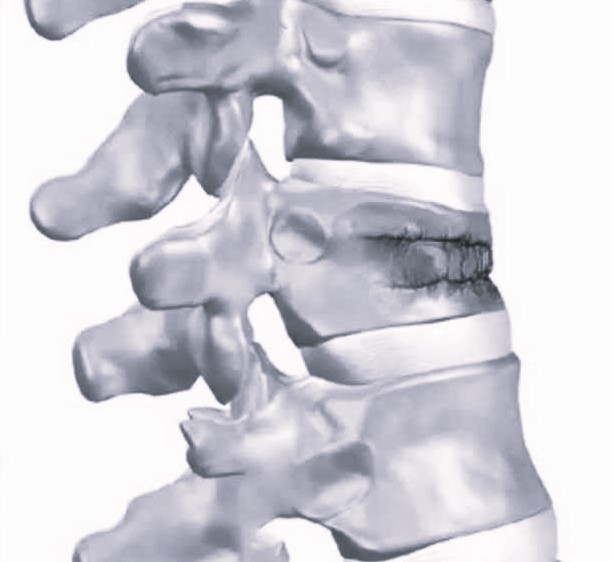

Стабильный перелом позвонка